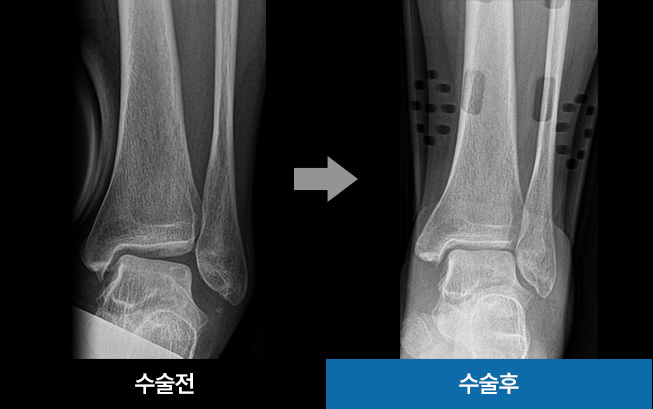

• 관절경적 발목 인대 봉합술

(최소 절개)

파열된 인대 주변에 뼈 조각이 없는 경우

관절경적 발목 인대 봉합 수술을 진행합니다.

3mm 초소형 관절경을 이용해 수술하므로

흉터와 조직손상도를 최소화하는 장점이 있습니다.

• 발목인대파열수술

(MBO)

가벼운 마취 상태에서 다친 인대를 봉합하여 복원하는 것이

목표입니다. 인대가 심하게 파열된 경우 또는 반복된 손상으로

발목 불안정성을 호소하는 경우에, 보존적·비수술적 치료에도

효과가 없을 시 수술을 진행합니다.